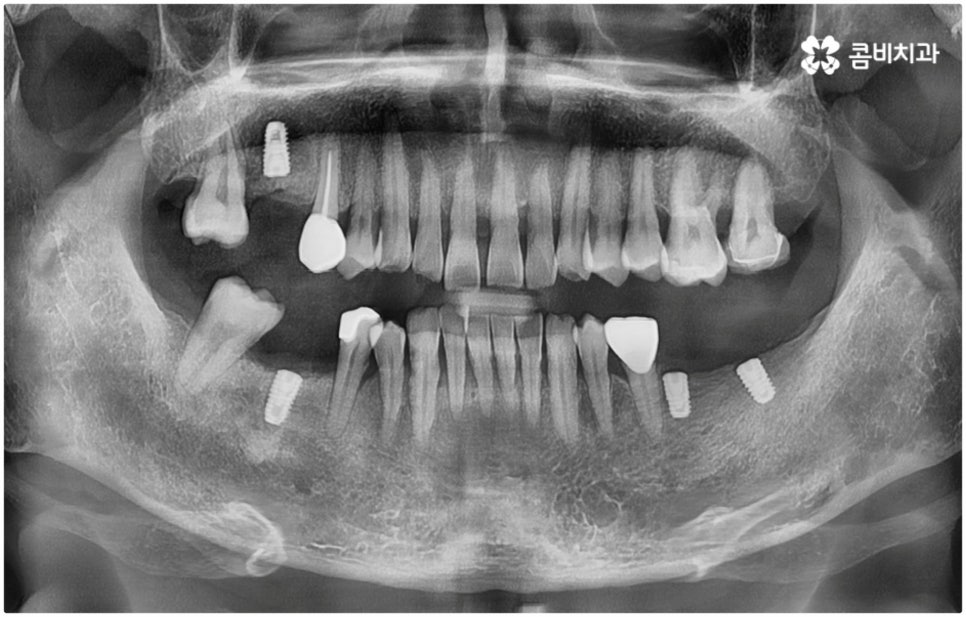

발치후 임플란트 즉시 식립 방식은 다른 임플란트와 달리 치아가 탈락한 빈 자리에 곧바로, 또는 조금 남아있던 뿌리를 뽑은 후 그 자리에 그대로 임플란트를 심기 때문에 공백 기간이 단축될 수 있고 임시치아 제작을 통해 해당 기간 동안 임시 틀니를 사용해야 하는 데서 오는 불편함 및 심미적인 어색함도 해결할 수 있어요. 또한 환자분들의 입장에서 마취 한 번에 발치와 식립 두 가지 과정이 함께 이뤄지기 때문에 통증과 두려움이 감소되고 치과에 내원해야 하는 횟수도 줄어들어 번거로움이 덜 할 수 있습니다.

치아가 빠진 순간부터 이를 받치고 있던 치조골이 서서히 흡수되기 시작하므로 영구치가 빠지고 나서 시간이 많이 지나게 되면 부족한 잇몸뼈 부분을 뼈이식으로 보충해 주는 과정이 추가적으로 들어가야 하지만 이미 뼈가 손상된 경우가 아니라면, 즉시 식립을 하면 그럴 필요가 없는 거예요. 또한 잇몸이 이미 내려앉은 후 수복을 하려면 잇몸 라인이 인위적으로 만들어질 가능성이 높아지는데 치조골 소실이 크게 일어나기 전에 임플란트를 심게 되면 주변 치아 및 잇몸과 보다 조화롭게 맞출 수 있어서 심미적인 부담도 덜 수 있어요.

게다가 발치 부위가 아물면서 자연스럽게 일어나는 인체의 치유 능력을 최대한 이용해 골결합을 유도하므로 부작용 발생 우려가 적고 임플란트의 인공 치근이 환자분들의 잇몸뼈에 좀 더 단단하게 유착될 수 있도록 안정성을 높일 수 있다는 장점도 있는데요.

개인차가 있지만 보통 발치후 임플란트 식립까지 2~3개월 정도의 회복 시간을 두게 되는데 바로 식립을 진행하게 되면 이 과정이 없어지므로 전체 기간을 획기적으로 단축시킬 수 있어요. 여기에 더해서 만약 내부에 자체 기공소를 갖추고 있는 치과에서 임플란트 시술을 받게 되면 보철물을 제작해서 받는 시간, 적응하면서 혹시라도 잘 맞지 않는 부분을 고치기 위해 왔다갔다 하면서 걸리는 시간도 줄어들 테니 기간적인 부분에서 걱정했던 환자분들의 부담을 훨씬 덜 수 있을 거예요.

발치후 임플란트 식립까지 회복 기간을 두지 않고 즉시 심게 되면 원래 치아가 있던 자리를 육안으로 확인한 후 그 자리에 곧바로 식립하므로 보다 정확한 위치를 잡을 수 있다는 장점도 있습니다. 하루 만에 식립과 임시치아까지 장착이 가능하여 간단한 식사도 할 수있다는 점에서 원데이 임플란트라고도 불리는 즉시 식립 방식은 지금까지 알아본 바와 같이 여러 장점을 가지고 있기 때문에 많은 분들이 선호하시고 있는데요.

즉, 해당 분야의 임상 경험이 풍부한 숙련된 의료진분들이 계신 치과에서 자신이 발치후 임플란트 즉시 식립 방식이 가능한지 부터 확인하실 필요가 있는데요. 만약 다양한 이유로 인해 발치 후 즉시 심는 것이 불가능한 케이스라고 한다면 상황에 맞게 뼈이식, 상악동 거상술, 잇몸 질환 치료 등 선처치들을 먼저 해 주고 나서 충분한 회복 기간을 두고 임플란트 시술을 진행해야 식립 성공률 및 지속 가능성을 높일 수 있습니다. 이렇게 환자분들 각각의 상황을 고려하지 않은 채 발치 후 즉시 식립을 무리하게 진행하게 되면 임플란트의 위치를 제대로 고정하는 데 어려움이 있어 해당 치아로 잘 씹을 수 없게 되고 얼마 지나지 않아 다시 쓰러지거나 주변 치아와 잇몸에 압박을 가해서 지속적으로 좋지 않은 영향을 주게 되는 등 문제가 커질 수 있으니 주의하실 필요가 있어요.

임플란트 후 수명을 늘리는 방법에 대해서 문의를 주시는 분들이 많이 있는데요. 지속성을 높이려면 말씀드린 것처럼 치료 자체의 정확성을 신경쓰는 것이 우선시 되어야 할 거예요. 즉 환자분들의 상황을 꼼꼼하게 검진하고 이에 맞는 방법으로 정확하게 식립하는 치과에서 임플란트 수술을 진행하는 것이 무엇보다 중요하다고 할 수 있습니다. 이를 위해서 환자분들의 잇몸뼈 두께나 밀도를 면밀하게 살필 수 있는 3D CT 기계를 갖추고 처음부터 끝까지 책임 진료하는 숙련된 의료진 분들과 함께 하시는 게 좋을 거예요.

이때 환자분들 각각의 정밀한 맞춤 계획을 세우고 이를 무리하지 않게 진행하기 위해서는 해당 치아의 잇몸뼈 상황 뿐 아니라 주변 치아 구조, 신경 위치 그리고 환자분들의 전체적인 구강 내 건강 상태 (치주 질환 여부 등) 를 자세하게 관찰하고 그 밖에 연령이나 기존 전신 질환 여부 (상용하는 약이 있는지 여부도 포함) 등 모든 부분을 충분한 상담을 통해 빠짐없이 파악하며 행여 중간중간 돌발 상황이 발생해도 침착하게 해결해 나가는 것이 중요하기 때문에 담당 의료진에게 굉장히 높은 수준의 기술력과 풍부한 노하우가 요구됨을 짐작할 수 있는데요. 이와 같이 매우 고난도 진료인 발치후 임플란트 시술을 보다 안정적으로 진행하기 위해서는 정밀 장비 보유 여부 및 의료진의 경력과 노하우를 철저하게 체크해 보시고 치과를 신중하게 선택하실 필요가 있어요.